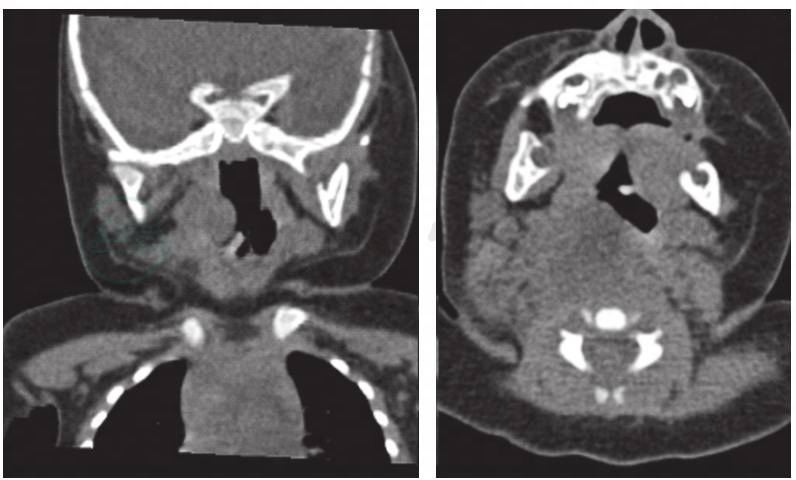

入笔者科室后予红霉素联合拉氧头孢钠抗感染治疗,完善相关检查:血常规提示白细胞 19.70×109/L;以淋巴细胞升高为主,CRP降至正常,脓汁细菌培养结果回报:金黄色葡萄球菌,其他病原学检查均为阴性,因对现用抗生素敏感,暂未予调整药物。喉CT+三维重建(图1)提示:右侧咽旁至颈部包块,中心坏死?淋巴结炎不除外,双侧颈部多发肿大淋巴结。颈部三维彩超提示右侧颈部软组织内可见窦道样包块,包块上端位于右后颈部,向前下方走行,下端位于气管后方,大小约5.6cm×1.8cm×1.4cm,边界模糊,形态不规整,包块周边呈低回声,彩色多普勒血流显像可检出血流信号,中心部呈液性伴密集点状回声,包块周边可见少许淋巴结,较大者约0.9cm×0.4cm,边界清,内呈低回声。左侧颈部可见少许淋巴结,较大者约1.2cm×0.6cm,边界清,内呈低回声。喉镜提示双声带光滑,声带运动正常,声门闭合可。双侧梨状窝、会厌谷及舌根黏膜光滑。下咽后壁膨隆,表面光滑。因影像学检查均提示咽部肿物,考虑为咽后壁脓肿,建议行咽后壁肿物穿刺探查,家属拒绝。入院第5天加用利奈唑胺抗感染治疗。吸气相呼吸困难逐渐缓解,入院第15天复查颈部三维彩超提示双侧颈部包块较前缩小,颈部肿大淋巴结较前缩小,复查血象较前下降,CRP降至正常。患儿出院。出院医嘱:口服利奈唑胺50mg/次,间隔12小时,连服10天;水调散双侧颈部包块处外敷,1周;10天后耳鼻喉科门诊复诊。

图1 喉CT+三维重建